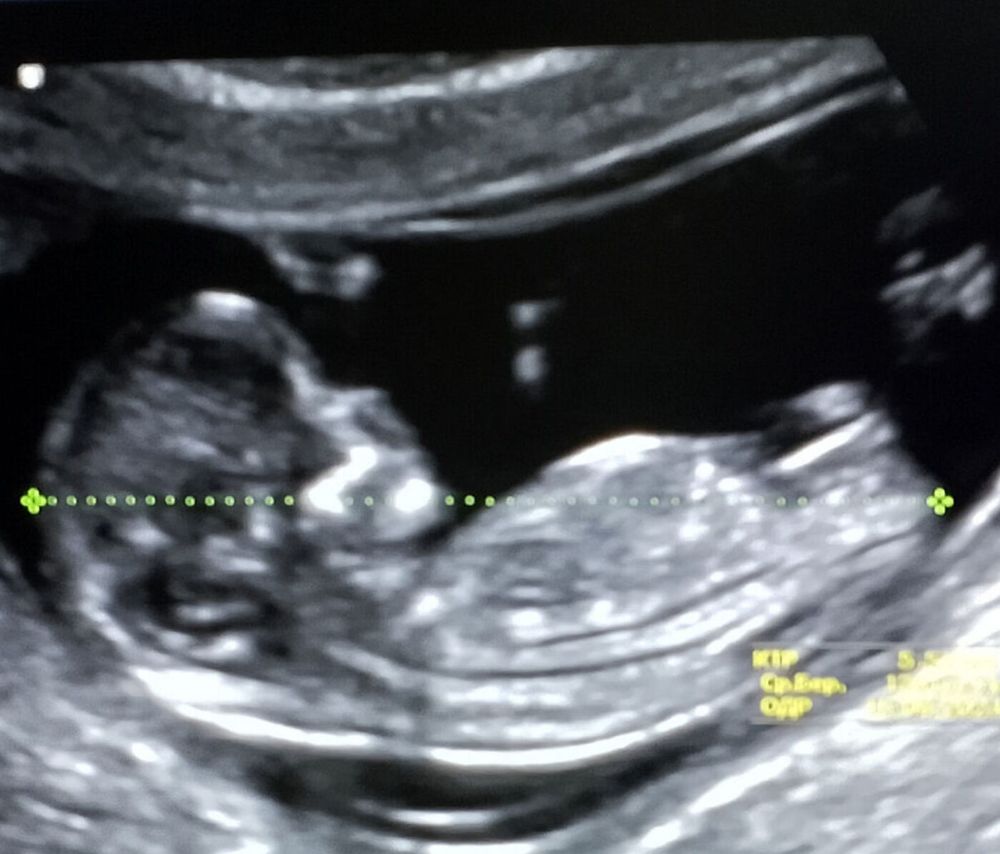

Дожили до скрининга )

У вас девочка , у меня такое же узи в 12 недель , на узи мне сказали девочка . Вот жду результат анализа крови чтобы подтвердили . Но узи точь в точь как ваше (ну богорок этот ) параллельно к позвоночнику . У нас тоже самое

А почему кажется?По снимку уже видно пол.Как они говорят на 99 процентов,но это же не мало)Или вам сказали,а хотите ещё раз посмотреть?)

Katarina , не, не говорили нам ничего ) это просто наша интуиция , что там девочка ) пойдем уже на 5д, чтобы точно увидеть )

Tanja, Дак видно,что девочка)Уж столько картинок пояснений в интернете,с этими острыми и не острыми углами)

Katarina , во, сына нашла, да , другой наклон этого бугорка Изображение

Family, да я тоже не сильна в них 😅 вот только вчера и узнала , ну судя по всему - девочка 🤔

1 скрининг Хорошие новости.